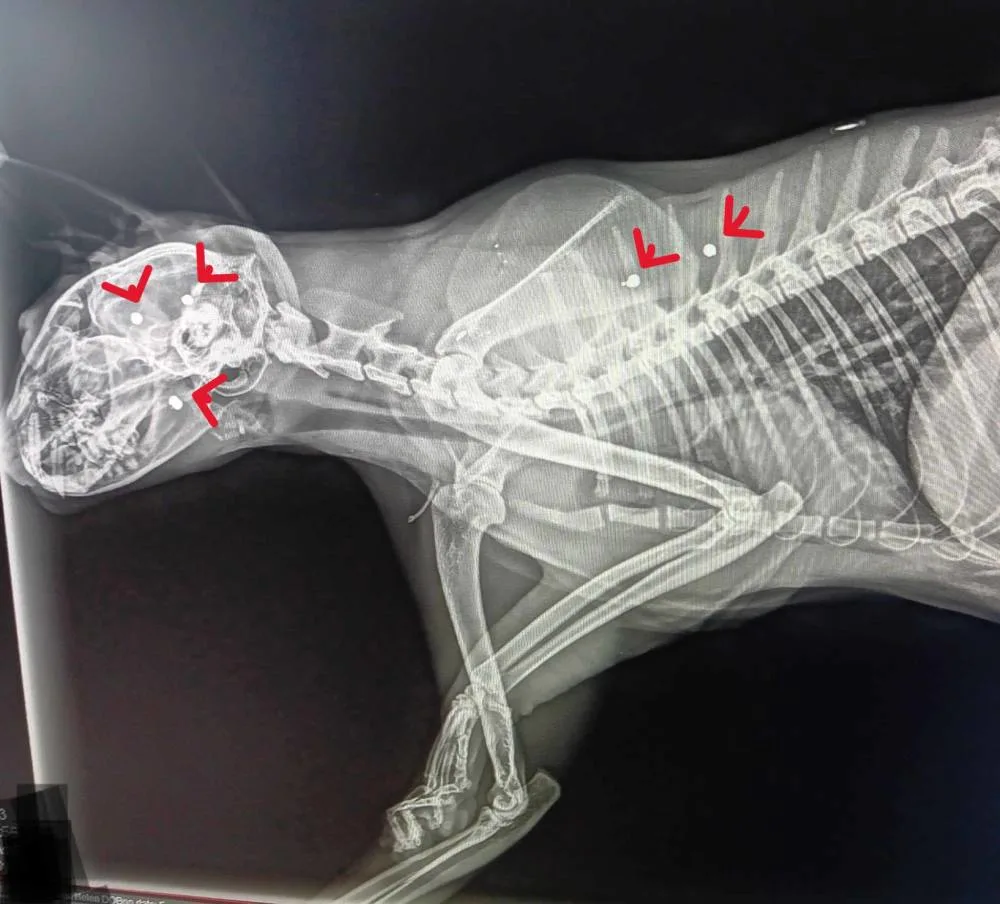

An x-ray was taken.

The room grew quiet.

The image revealed horrors unseen.

The pellet was still there.

Still inside her skull.

But it was not alone.

There were many.

Scattered through her jaw.

Her head.

Her body.

She had not been shot once.

She had been shot many times.

Or with buckshot.

Her small body had absorbed violence meant to destroy.